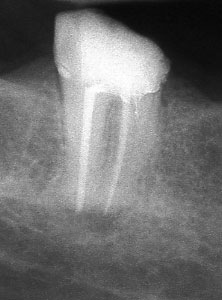

Ако при диагностична рентгенография се установи, че даден канал не е запълнен до физиологичното стеснение, е необходимо да се проведе повторно ендодонтско лечение.

В някои случаи недобре запълненият коренов канал е показание дори за отстраняване на протезни конструкции (корони и мостове) в които е включен съответният зъб.